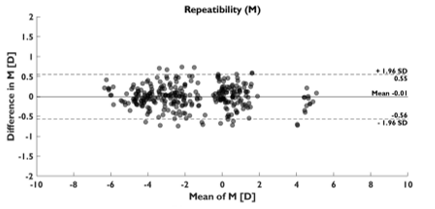

PurposeModern autorefractors have demonstrated high accuracy and higher repeatability than manifest refraction in adults yet are not considered precise enough to substitute the gold standard, even in low-resource settings where there is a severe shortage of experienced refractionists. This work evaluates a novel approach that combines dynamic wavefront aberrometry data, acquired using an affordable portable autorefractor, with the analysis of retinal image quality metrics (IQMs) to predict subjective refraction. Methods56 subjects (34±14 years) were recruited for the analysis. Each participant underwent standard clinical refraction followed by a 10-second video acquisition using a QuickSee (QS) wavefront aberrometer (PlenOptika, USA). Shack-Hartmann images of each video for the right eye were processed to obtain Zernike coefficients up to the 4th order. Coefficients obtained for each image were mathematically corrected with the closest sphero-cylindrical correction and the residual wavefront error was used to calculate the Point Spread Function (PSF) and IQMs (e.g., Strehl Ratio) describing some performance parameter of the corrected eye. Since each IQM is part of a dynamic sequence, it is possible to build a dynamic signal for each metric which contains information about fluctuations in image quality during the measurement. The final refraction is obtained as the average of the refractions corresponding to the images whose IMQs provided optimal performance. ResultsThe proposed method reduced the differences between QS and manifest refraction. Specifically, for spherical equivalent refraction (M) (Table 1) a 79% average reduction in MBE together with moderate average improvements for MAE (10.3%), LOA (5%), and percentage of agreement within 0.25D (8.8%) and 0.5D (6.3%) were found for all IQMs evaluated. ConclusionsThe proposed algorithm behaves as an efficient filter which selects those measurements within the dynamic sequence that are more representative of the manifest refraction of the patient. |

PurposeHigh repeatability portable autorefractors may enable effective deploy of global-health initiatives to mitigate uncorrected refractive error worldwide. For example, in studies to evaluate the effectiveness of different measures, repeatability has a direct impact on the statistical power and sample size required, while in screening applications, contributes to increased sensitivity and specificity. This work presents a preliminary assessment of the inter- and intrasession repeatability of an affordable autorefractor (QuickSee, PlenOptika Inc) under two separate measurement conditions, with and without fogging lenses. Methods6 volunteers (29,8 ± 8,1 years old) were measured at 2 different sessions spaced 1-week. Each subject was tested 6 times per session with the QuickSee, 3 times in standard mode and 3 using a modified version of the device eyecup to allow over-refraction through fogging lenses (+2.0 D). Intersession measurements were spaced 5 minutes apart and the complete alignment procedure was repeated for each measurement. After converting autorefractor readings into power vectors (M, J0, J45), repeatability was evaluated using the Bland-Altman method to compare differences between all possible combinations from each subject (inter- and intrasession). Repeatability coefficients (RPC), estimated as the 95% limits of agreement, and the mean absolute errors were also evaluated. In all cases, only results for the right eyes were analyzed. ResultsParticipants had an average Spherical Equivalent (SE) refraction of -0.75 ± 2.06 D, (Min -5.11 D, Max 0.175 D). A total of 36 samples per dataset were obtained for the intrasession analysis while 54 samples per dataset were used in the intersession comparison. In all cases the mean difference was practically 0 indicating no bias for any of the vector components. SE RPCs for intrasession test were 0.15 D in standard mode and 0.29 D with the fogging lenses. Intersession RPCs were 0.29 D and 0.4 D without and with the fogging lenses, respectively. Detailed results for all vector components are shown in Table 1. ConclusionsThis preliminary analysis shows that the device can provide excellent RPCs in standard mode, which decrease moderately with the use of the fogging lenses. Further work exploring improvements in the eyecup design and measurement averaging techniques may further enhance the RPC values in over-refraction mode. |